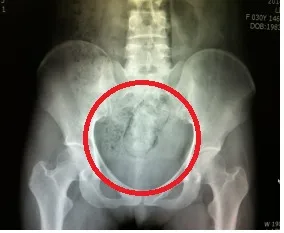

몸속에 마약을 은닉한 사진. 서울신문 DB